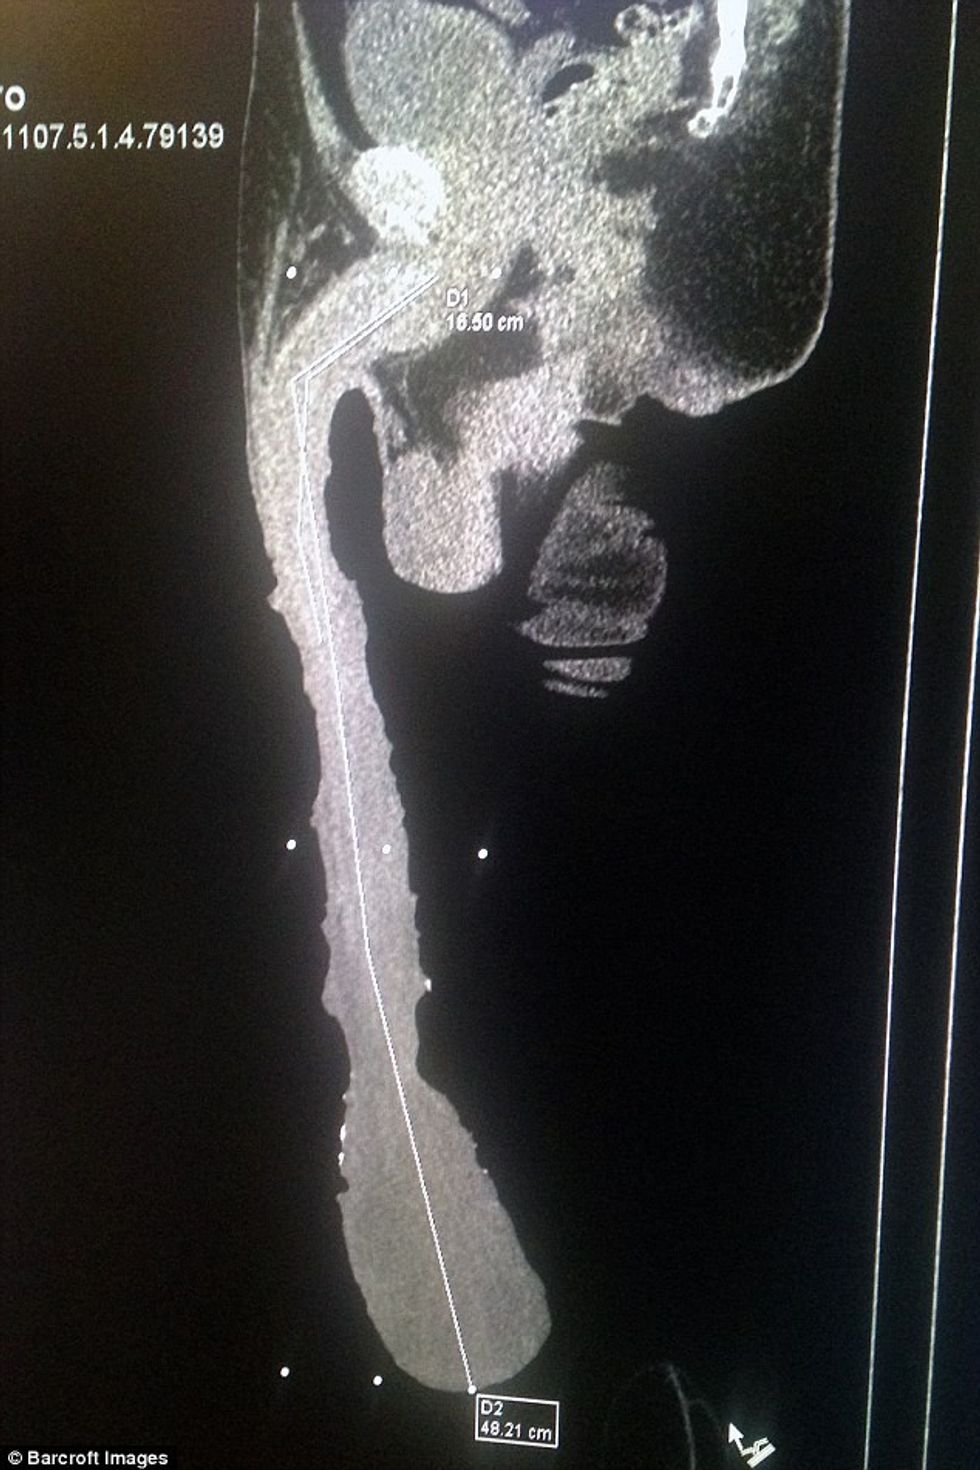

Siç shkruajnë mediat e huaja, përcjell Telegrafi, Roberto Esquivel Cabrera, 54, nga Saltillo, Meksikë, ka një penis rreth 50 centimetra të gjatë.

Penisi i tij gjysmë metër i gjatë thuhet se ka thyer rekordin jozyrtar që besohet se i përkiste aktorit amerikan Jonah Falcon, penisi i të cilit ishte rreth 25 centimetra në gjendje normale dhe rreth 35 centimetra gjatë ereksionit.